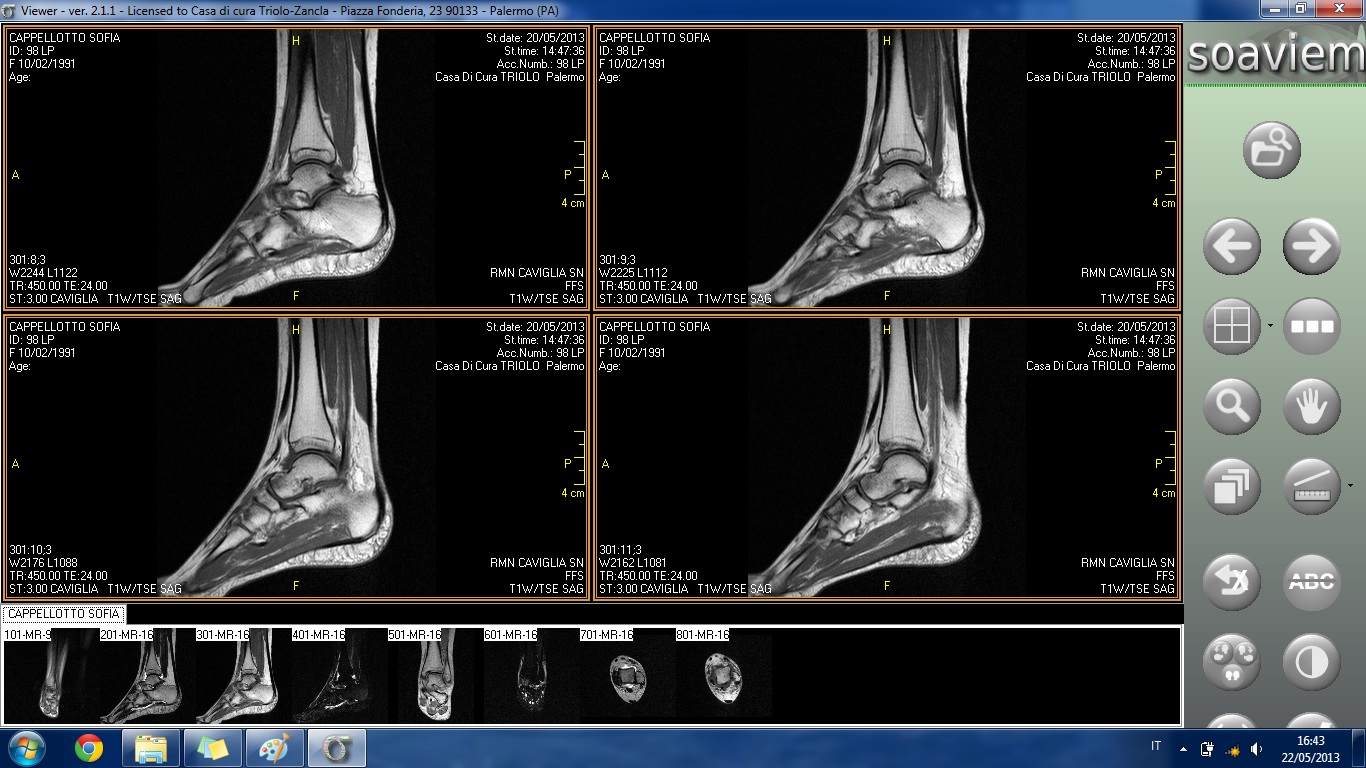

HO FATTO UNA RISONANZA E RIPORTO DI SEGUITO INDICAZIONI TRATTE DAL REFERTO E ALLEGO ALCUNE IMMAGINI:

ESAME ESEGUITO IN TECNICA SE, TSE E STIR MEDIANTE SCANSIONI T1 E T2 PESATE CONDOTTE SUI PIANI ASSIALE, CORONALE E SAGITTALE.

ALTERAZIONE DI SEGNALE DELLA TESTA ASTRAGALICA IN RELAZIONE ALLA PRESENZA DI AREA DI ELEVATO SEGNALE IN STIR DA RIFERIRE AD IPEREMIA TRABECOLARE COME IN ESITI DI IMPATTO OSSEO. REPERTO DI ANALOGHE CARATTERISTICHE DI SEGNALE SI RIVELA A CARICO DEL VERSANTE ANTERIORE DELL'EPIFISI DISTALE DELLA TIBIA ED A CARICO DEL MALLEOLO PERONEALE.

SENSIBILE QUOTA FLUIDA ENDOARTICOLARE.

IL LEGAMENTO PERONEO-ASTRAGALICO ANTERIORE NON APPARE IDENTIFICABILE NELLA PROPRIA CONTINUITÀ ANATOMICA COME PER LESIONE. TUTTAVIA IN RELAZIONE AL RECENTE EPISODIO TRAUMATICO SI CONSIGLIA RIVALUTAZIONE ETG A DISTANZA DI TEMPO. IL LEGAMENTO PERONEO-ASTRAGALICO POSTERIORE ED IL LEGAMENTO DELTOIDEO, SEPPURE INSERITI, MOSTRANO ASPETTO DISOMOGENEO COME PER ESITI DISTRATTIVI.

BEN INSERITO IL LEGAMENTO PERONEO-CALCANEARE.

REGOLARE ASPETTO DEL LEGAMENTO TIBIO-PERONALE INTERNO.

REGOLARE ASPETTO MORFOSTRUTTURALE DEI TENDINI PERONEI E DEI TENDINI DEL COMPARTO ANTERIORE E MEDIALE NEL TRATTO ESPLORATO.

SOSTANZIALMENTE REGOLARE ASPETTO MORFOSTRUTTURALE DEL TENDINE ACHILLEO.

NON SIGNIFICATIVE ALTERAZIONI DEL TROFISMO DEI RESTANTI CAPI SCHELETRICI ESAMINATI.

REGOLARE ASPETTO DELLE STRUTTURE DEL SENO DEL TARSO.